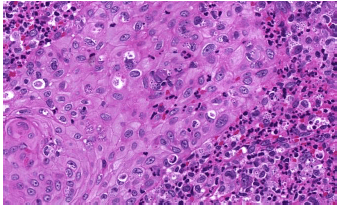

Homem, 39 anos, com relato de lesões placas violáceas nos membros inferiores. Assinale a alternativa que apresenta o diagnóstico que a figura abaixo ilustra.

Provas